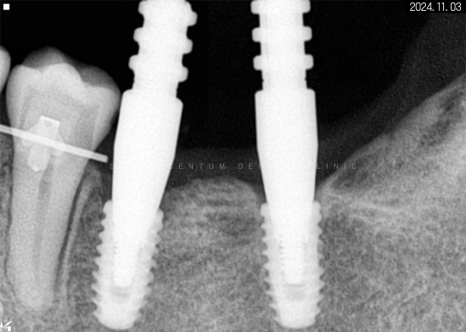

따라서 적정 시기에

CT를 촬영해 치조골 폭과 밀도를

철저하게 분석한 다음 정확한 자리를 선정하고

임플란트 식립을 진행했습니다.

하악 좌측 사랑니 발거 후

임플란트가 필요한 부분들에

픽스처를 견고하게 식립해 드렸습니다.

*기다란 막대기는 뿌리 끝 길이를

측정하기 위해 사용한 도구입니다.